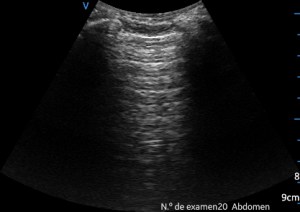

Tras ver las imágenes vas a comprobar como la estructura está dañada, pero primero quiero que veas como se ve una ecografía normal del bazo, ecoestructura que, si estás empezando se resiste, su ubicación en el abdomen, protegido por las costillas, cercano al ángulo esplénico del colon, hace que sea complicado, ten paciencia, solo con esto conseguirás estudiarlo bien, es cuestión de técnica.

Estas dos imágenes superiores son la normalidad. Corte axial y longitudinal del Bazo. Homogéneo, sin lesiones, grande sin llegar a la esplenomegalia. Bazo de libro.